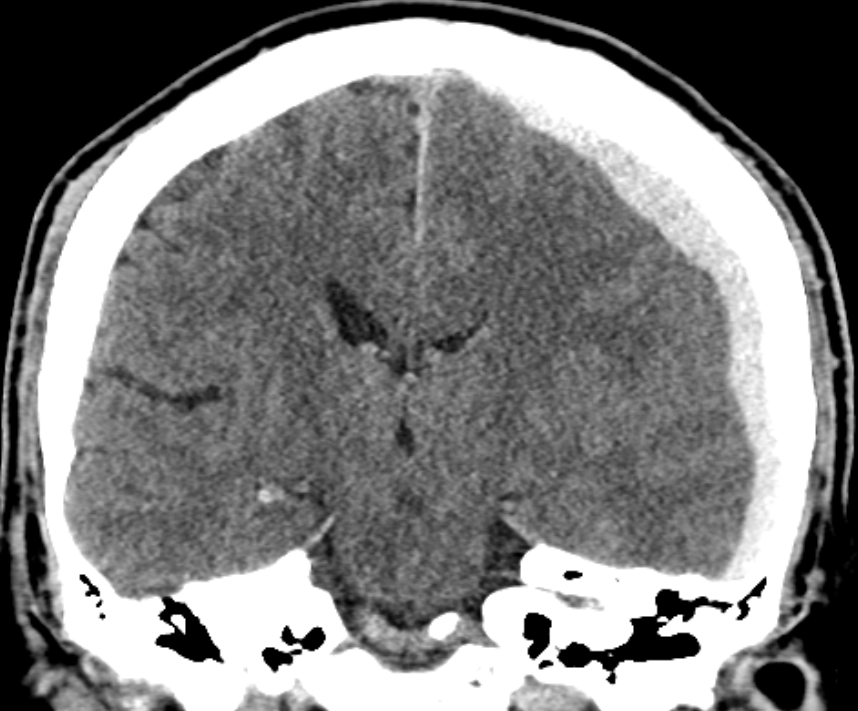

4.파열된 정맥에서 혈액이 경막하강에 고여 CT 상 반월상 형태로 나타남.

6.혈종이 지속적으로 증가하면 뇌 구조물이 반대편으로 밀리는 Midline shifting이 발생하며, 이는 중증 신경학적 손상의 지표로 간주함.